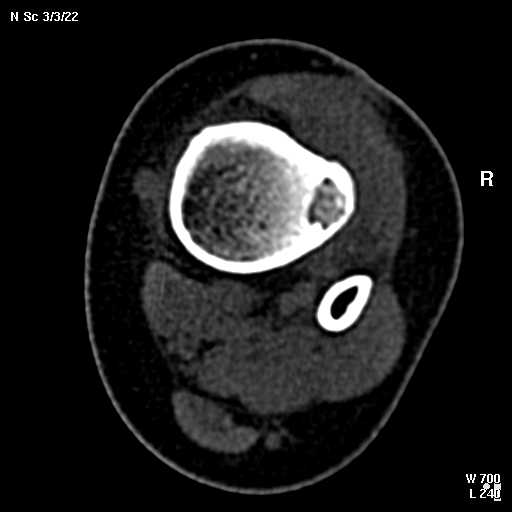

С подозрением на хондрому большеберцовой кости левой голени выполнена компьютерная томография. На серии томограмм получены изображения дистальных отделов левой голени. В дистальном метафизе на уровне нижней трети по латеральному краю определяется кортикальный очаг деструкции размерами 1,3x0,5x0,8 см. На уровне очага деструкции отмечается истончение кортикального слоя, без признаков его разрушения. Кость на уровне очага вздута. Структура окружающих мягких тканей не нарушена, объемных образований не определяется. Крупные нервные стволы и просветы крупных сосудов хорошо дифференцируются. Кожа и подкожно-жировая клетчатка не изменены.Заключение: КТ - признаки кортикального остеолитического очага деструкции в дистальном отделе метафиза левой большеберцовой кости без признаков разрушения кортикального слоя (остеогенная саркома?).19.11.2002 г. осмотрена онкологом, выставлен диагноз: саркома левой большеберцовой кости?Лабораторные исследования: - ОAK от 06.11.2002 г. - L - 11,3х109; эр. - 4,47хЮ12; НЬ - 117 гр./л; Ht - 33,6%; тр. -208x109; СОЭ - 38 мм./час, э-1; п-7; с-55; м-4; л-33.В отделении детской онкологии 11.12.02 выполнена операция: секвестр-некрэктомия н/3 левой большеберцовой кости.Послеоперационный период без осложнений.Проведено лечение. Линкомицин 150 мгхЗ р./д., обезболивание (анальгин, димедрол). Швы сняты 23.12.02, заживление первичным натяжением.Получен результат гистологического исследования: хронический остеомиелит. Данных за онкопроцесс нет.На приеме врача ортопеда поликлиники с жалобами на усиление болевого синдрома 03.01.03. Наложена задняя гипсовая лангета. Назначен противовоспалительная терапия, препараты Са и кальцийтониновые препараты. На фоне проводимого лечения болевой синдром купировался. На серии рентгенограмм (январь-февраль-март) На нижней трети левой большеберцовой кости наличие дополнительного кортикального очага диструкции с размерами 1.5x0,5 см., в динамике отмечается увеличение в размерах.С подозрением на рецидив хронического остеомиелита большеберцовой кости левой голени выполнена компьютерная томография.19/03/2003 На серии томограмм получены изображения дистальных отделов нижней трети левой голени и мягких тканей.В метафизе определяется очаг деструкции с четкими, неровными контурами, неоднородной структуры, за счет костных балок, размерами 1.8x1.8x2,4 см, плотностью 29 ед Н.В дистальном методиафизе. по латеральному краю, определяется кортикальный очаг деструкции, размерами 0,6x0,5x2,0 см, неоднородной структуры, за счет наличия фиброзных и костных балок, кортикальный слой истончен, без признаков разрушения.Структура окружающих мягких тканей не нарушена, объемных образований не определяется. Крупные нервные стволы и просветы крупных сосудов хорошо дифференцируются.Кожа и подкожно-жировая клетчатка не изменены.ЗАКЛЮЧЕНИЕ:КТ-картина состояния после операции. Формирование постоперационной, внутрикостной кисты. КТ-признаки объемного образования нижней трети левой большеберцовой кости, вероятнее всего фиброзная дисплазияРЕКОМЕНДАЦИИ: МРТ левого голеностопного сустава с захватом нижней трети голени.Лабораторные исследования: OAK от 05.03.2003 г. - L v 7.0х109; эр. - 4,74хЮ12; НЬ - 130 гр./л; Ht - 37%; тр. -274x109; СОЭ - 4 мм./час, э-1; п-1; с-53; м-3; л-42.Вопросы: уточнение диагноза? (хр.остеомиелит, обострение? Или все таки онкопроцесс) какие исследования провести? тактика лечения? КТ-снимки во вложении. Заранее благодарен!С уважением, Н.П.Козел.